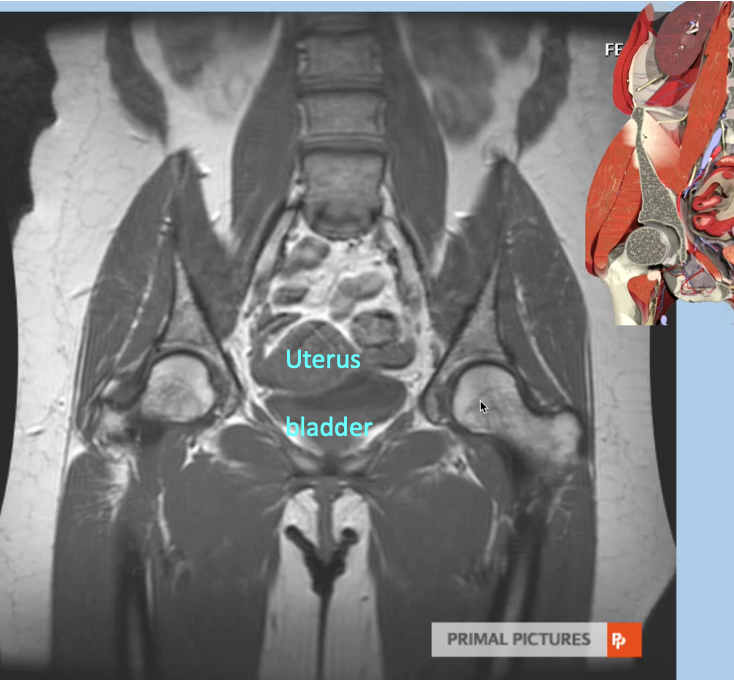

Q

Imaging modality & complete the labels

A

Coronal MRI

11

Imaging modality and what is seen in the ovaries

T2 weighted MRI (fat & water are white)

Ovaries containing follicular cysts